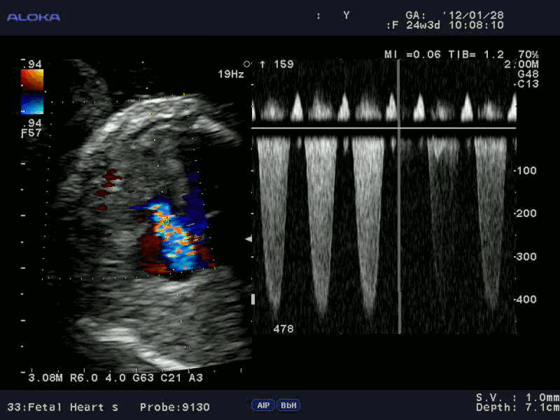

Цветовое допплеровское картирование является разновидностью ИВ допплерографии, при которой кровоток или движение миокарда изображаются разными цветами (обычно красным, синим и зеленым) или их комбинацией, что зависит от скорости, направления и наличия турбулентности.

В каждом участке изображения частотный сдвиг измеряется, преобразуется в цифровой формат, автоматически сопоставляется с заданной цветовой схемой (автокорреляция) и выводится на экран на фоне двухмерного изображения. При оценке кровотока в полостях сердца поток, направленный к датчику и имеющий положительный частотный сдвиг, кодируется оттенками красного. Кровоток, направленный от датчика и имеющий отрицательный частотный сдвиг, колируется оттенками синего.

Оценки в пределах каждого первичного цвета задаются высокими скоростями, не достигающими предела Nyquist. Когда скорость становится выше этого предела, появляется искажение цвета. Турбулентность отражает степень отклонения скоростей в определенной области от средней скорости и кодируется обычно оттенками зеленого.

В связи с этим аномальный кровоток легко распознать по комбинации многочисленных цветов, соответствующих направлениям, скоростям и степени турбулентности. Ширину и размер аномального внутриполостного кровотока используют для оценки степени регургитации на клапанах или выявления впутрисердечных шунтов.

Преимущества допплерографии особенно очевидны в акушерской практике. Метод позволяет изучать состояние кровотока плода, маточных артерий и пуповины, а так же регистрировать ЧСС плода.